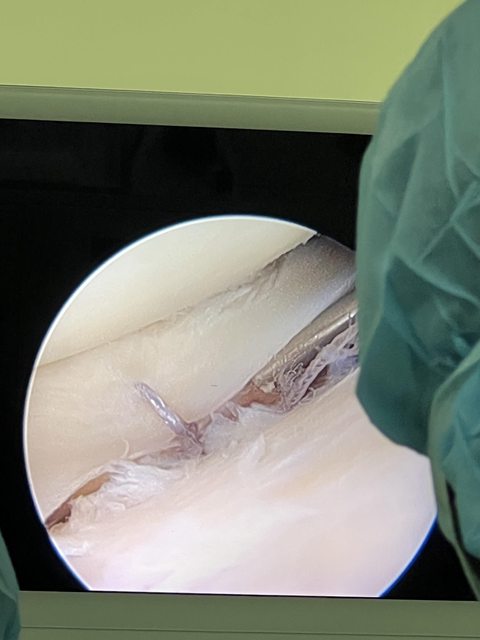

小弟弟我剛好從事運動醫學相關,這幾天也是跟了不少半月板修復術。 半月板修復後基本上會打石膏兩個月,加上復健及訓練大概要3個月左右才會回歸。 4週後有可能只是先照影像看復原的情形決定回歸時程表。 附上一張半月板縫合的照片 https://i.imgur.com/GYZo1hc.jpg

yowhatsupsli: 樓上冷靜 那是膝關節軟組織 02/07 08:40